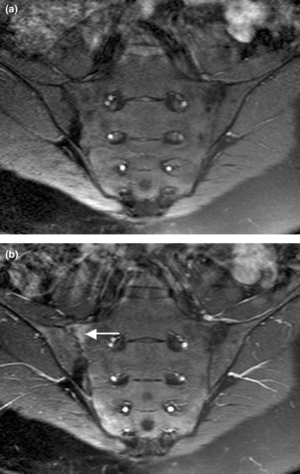

يبدأ التهاب الفقار المقسط في صغار البالغين بألم مبهم في أسفل الظهر، ويبوسة مديدة تالية للراحة تتحسن جزئياً بالحركة والتمارين الرياضية. ينتشر الألم إلى الاليتين والقسم الخلقي من الساقين. كما يحدث ألم في القفص الصدري بإصابة المفاصل الغضروفية المركزية فيه، وقد يكون لهذا الألم صفات جنبية، ويظهر الألم أيضاً في مفاصل قبضة القص Manubriosternal والمفاصل القصية الترقوية. إن التهاب ارتكازات الأربطة والأوتار عرض بارز وقد يكون العرض الأول. وينجم الألم عن التهاب الأصابع Dactylitis ' أو وتر أشيل، أو اللفافة الأخمصية، أو عرف الحرقفة iac أ I Crest. تكون الإصابة المفصلية بشكل الام مفصلية، أو التهاب مفاصل عديد، يصيب المفاصل الزليلة الدانية وبشكل غير متناظر كالكتفين والمرفقين والركبتين ونادرا المفاصل الصغيرة القاصية. وتترافق هذه الإصابة بيبوسة صباحية مديدة وأحياناً بتورم الا أنه من غير الشائع حدوث إصابة مفصلية تاكلية شديدة.

يحدث التهاب العنبية الأمامي في حوالي ربع المرضى، ويتظاهر بألم واحمرار وخوف من الضياء، وتكون هذه الإصابة نوبية، وحيدة أو ثنائية الجانب. يبدي الفحص السريري نقصاً في حركية العمود الفقري، مع فقد تام أو جزئي للقعس القطني الفيزبولوجي، وزيادة في الحدب الظهري. أما المظاهر المتأخرة فتشمل تحدد حركة جدار الصدر في الشهيق العميق (أقل من 2.5 سم) مع انحناء تدريجي، وثبات العمود الفقري والرأس في وضعية العطف. ويمشى المريض جاراً قدميه Shuffling Gait مع تفاوت شدة إصابة المفاصل المحيطة.[2]